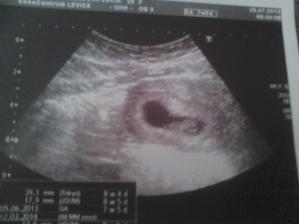

@nonika ano ak vsetko pojde dobre tak ano dakujjem

Luci blahoželám a prajem veľa zdravíčka 🙂